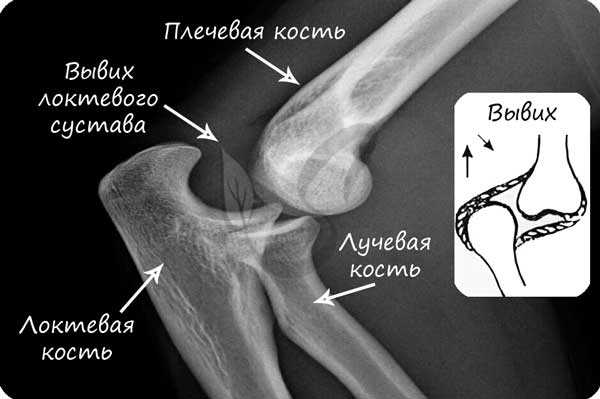

В норме кости могут смещаться относительно друг друга в суставе, однако при травме, слишком резком и сильном движении это смещение может быть слишком сильным: в результате нарушается соприкосновение суставных поверхностей. В таком случае говорят о возникновении вывиха.

Вывих - смещение суставных концов костей, как с нарушением целостности суставной капсулы, так и без нарушения.

Техника оказания медицинской помощи при вывихах:

- Иммобилизация (лат. immobilis - неподвижный) поврежденной конечности с помощью косынок, шин (поддерживающие крепления), путем прибинтовывания конечности к здоровой части тела

- Холод на область поражения, дать обезболивающее (убедившись в отсутствии аллергии)

- Доставить пострадавшего к врачу или вызвать скорую помощь

Перед вправлением вывиха следует делать рентгенологическое исследование, чтобы убедиться в отсутствии переломов костей, которые иногда сопутствуют вывиху.